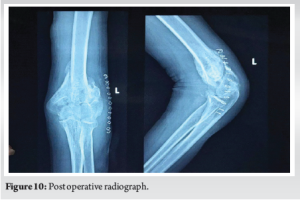

The immediate post-operative period was uneventful and was started on active left elbow mobilisation exercises on POD 1. Prophylaxis for the prevention of HO was started Indomethacin 25 mg for 3 weeks. Post-operative radiograph was taken and was satisfactory (Fig. 10). Sutures were removed on POD 14 and surgical site wound recovery was uneventful.